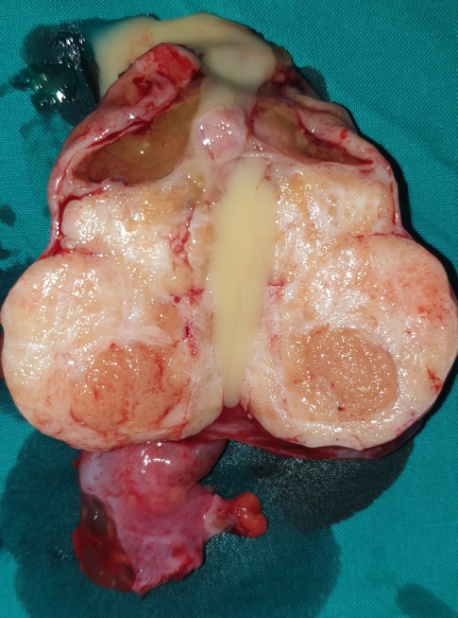

Μακροσκοπική εικόνα δεξιού εξαρτήματος – Καλοήθες νεόπλασμα Brenner (Ευγενική παραχώρηση Dr. V. Penopoulos)